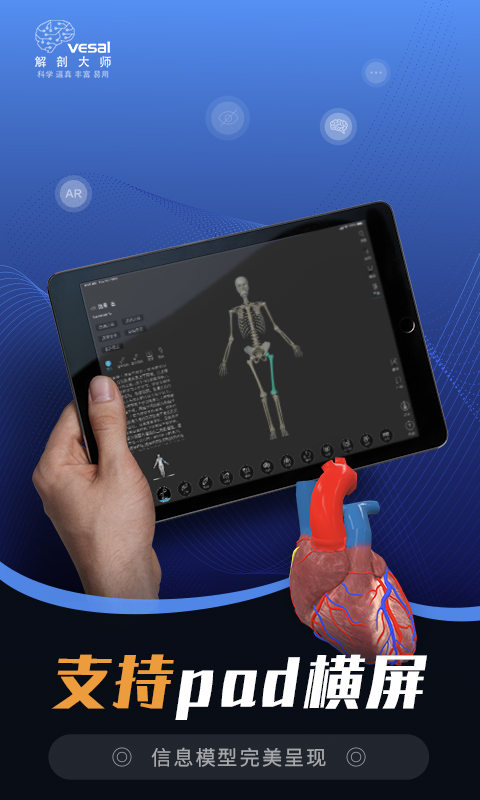

3D男女模型支持AR学习模式,提高学习效率

电脑端支持PPT课件插入3D模型,使教学脱颖而出